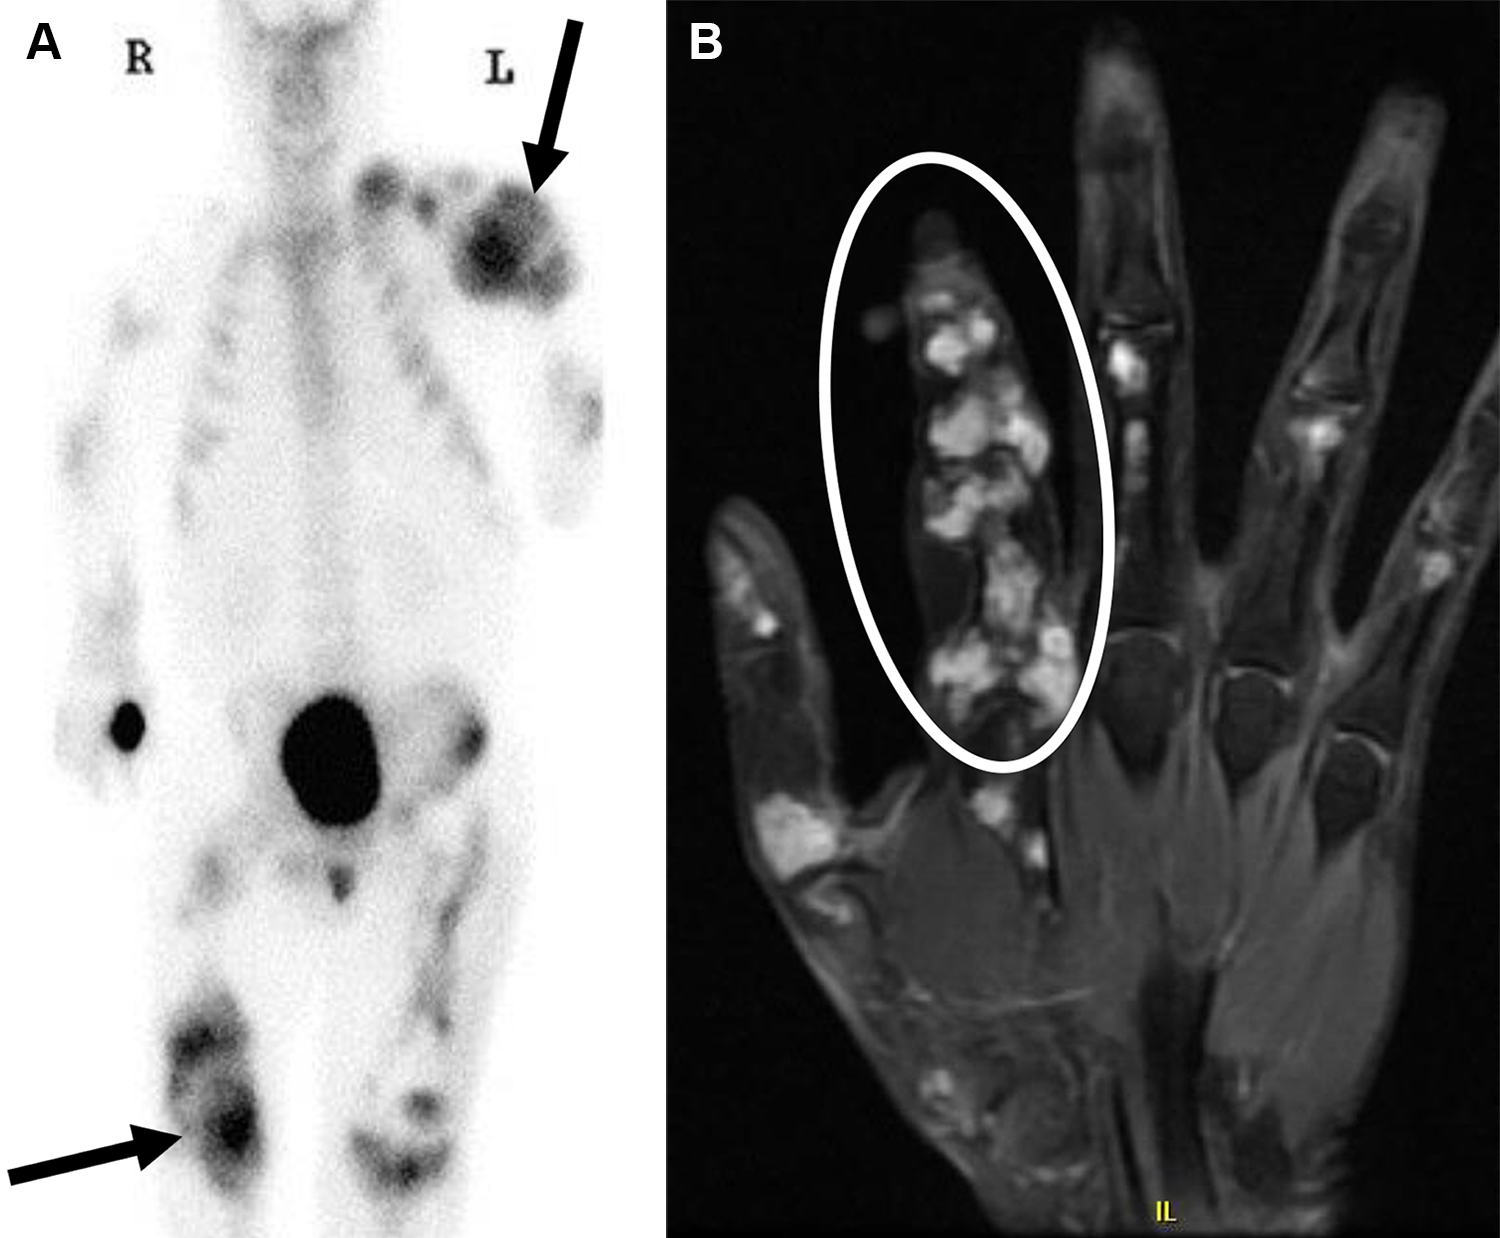

Sindrome di Maffucci in una donna di 25 anni.

L’esame scintigrafico total body evidenzia un’intensa ipercaptazione multifocale in corrispondenza delle aree ossee espanse, localizzate prevalentemente a livello epifisario e metafisario (specialmente a carico di arto superiore sinistro e arto inferiore destro).

La risonanza magnetica definisce nel dettaglio le lesioni della mano sinistra, identificando masse espansive (iperintense in T2) che corrispondono agli encondromi.

Diagnosi differenziale: sia la sindrome di Maffucci che la malattia di Ollier presentano encondromatosi multipla (con matrice cartilaginea che spesso calcifica assumendo aspetti ad “anello e arco” in TC o RX).

Il reperto dirimente per la sindrome di Maffucci è l’associazione degli encondromi con emangiomi dei tessuti molli (malformazioni vascolari che frequentemente sviluppano calcificazioni interne note come fleboliti).